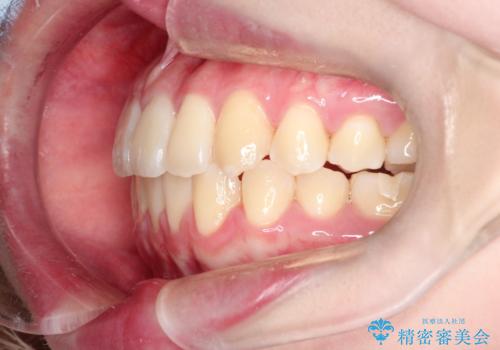

【インビザライン】歯を抜かずにできるだけ前歯を下げたい

- 前歯の前突を主訴に来院されました。

インビザライン を用いて、歯並びの改善を行うことができました。